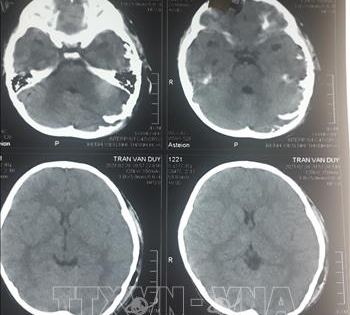

Phẫu thuật thành công cho bé 4 tuổi bị chó cắn hở sọ não

Bệnh viện Nhi Thanh Hóa cho biết, đơn vị vừa điều trị thành công cho bệnh 4 tuổi bị thương do chó cắn khiến sọ não hở ở vùng chẩm và thái dương trái.